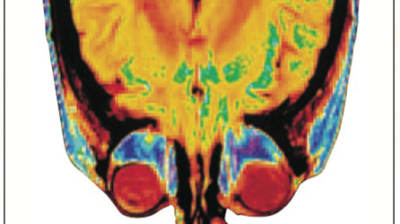

LumaSense Technologies, Santa Clara, CA, offers the Mikron MikroSHOT portable thermal imaging camera, a radiometric thermal imager that offers pocket-sized portability. The Thermal-On-Visible mode allows for radiometric...